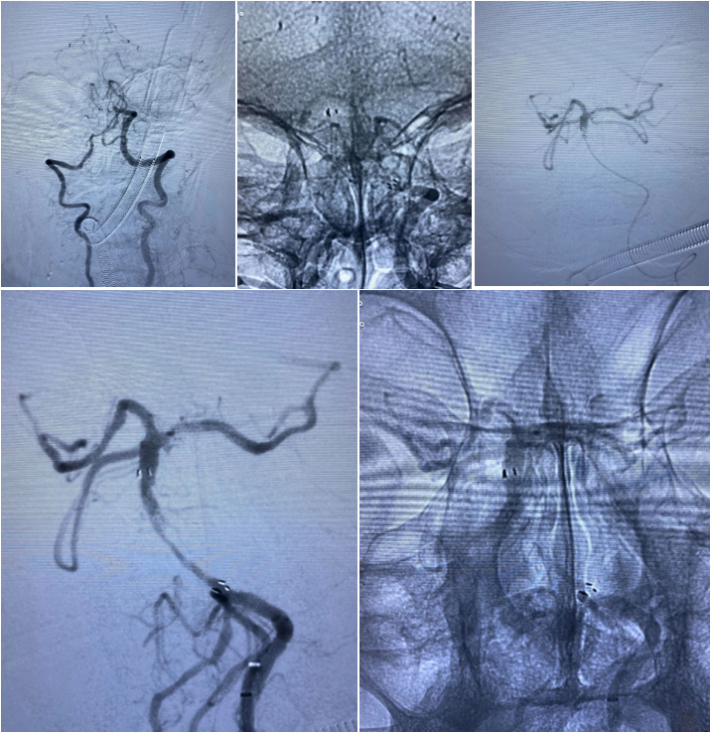

经过尝试,支架导管Rebar 18➕Synchro导丝200cm通过变形严重的原支架Enterprise 2。

打开取栓支架。

Solitaire AB 4mmx20mm成功挂住Enterprise 2。

尝试回收支架至5F Navien,牵扯力量比较大,提心吊胆。

经反复收拉尝试,最终取出Enterprise 2支架。

Enterprise 2支架在血管内两端严重变形,反折的Mark恰好被Solitaire AB支架咬合取出。

造影未见出血,血流良好,原狭窄在第一次支架时球囊扩张,现在狭窄已缓解。狭窄远端血管内膜稍不光滑。观察30min,血流稳定,为避免再放支架血栓,同时本次预后尚未知,暂不植入第二枚支撑支架,予以替罗非班注射液应用。